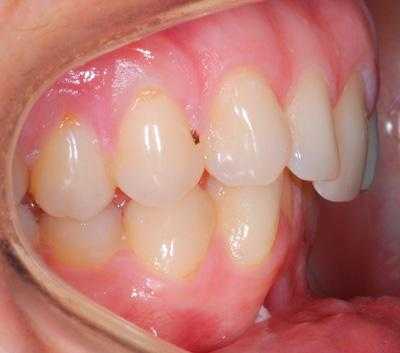

В полости рта дистальный прикус определяется по выступающим вперед верхним фронтальным зубам. В норме, при ортогнатическом прикусе, верхние резцы перекрывают нижние примерно на 1/3. При дистальной патологии между верхними и нижними резцами образуется расстояние — «саггитальная щель».

- II подкласс — передние зубы растут по направлению назад, смыкаются с нижними резцами, саггитальная щель отсутствует.

Определяющими внутриротовыми признаками дистального прикуса служат выдвижение вперед верхних фронтальных зубов; несмыкание верхних и нижних резцов с наличием между ними сагиттальной щели; нарушение взаимного расположения боковых зубов в переднезаднем направлении. В чистом виде дистальный прикус встречается редко; гораздо чаще он сочетается с аномалиями положения зубов, диастемой, тремами, глубоким, открытым или перекрестным прикусом, готическим нёбом.